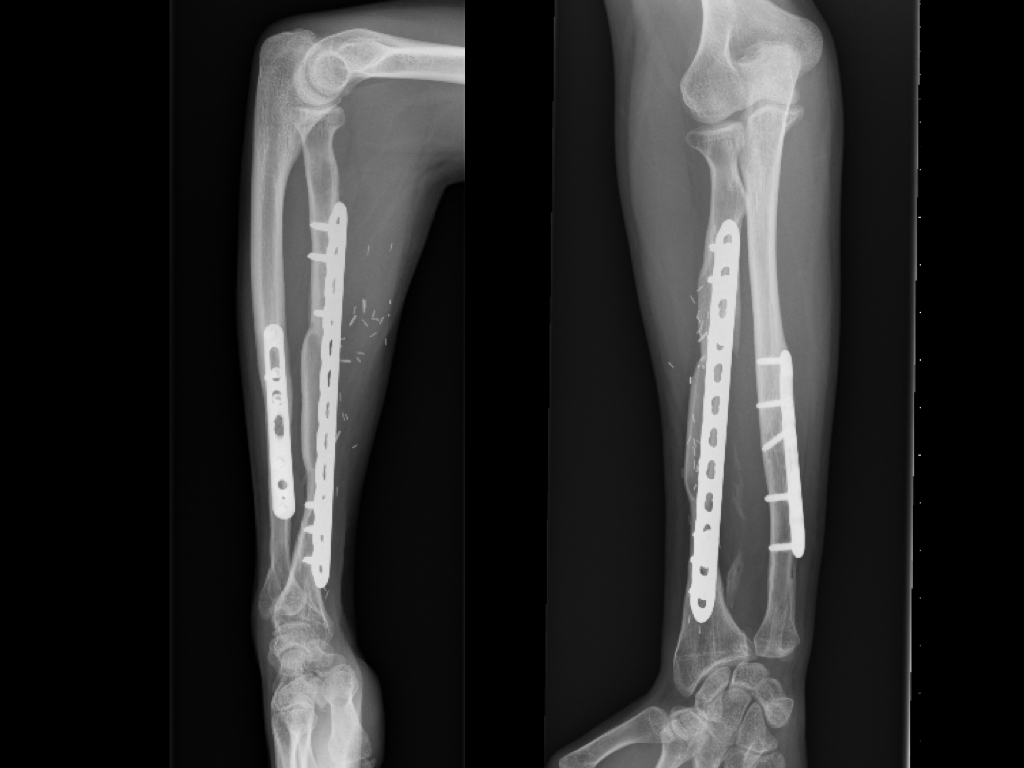

Introducción Los defectos óseos mayores a 6 cm en los huesos largos resultan en un problema difícil a reconstruir del miembro superior. Entre las opciones se encuentran: el injerto óseo alogénico, la utilización de la técnica de Masquelet y el injerto vascularizado de peroné. El peroné vascularizado se ha convertido en el principal método de reconstrucción por sus ventajas biológicas. El objetivo del presente estudio fue evaluar la tasa y el tiempo de consolidación ósea y las complicaciones asociadas en una serie continua de pacientes. Material y MétodosSe realizó una revisión del registro para identificar a todos los pacientes que se sometieron a una reconstrucción con peroné vascularizado durante un periodo de 5 años. Se incluyeron a todos los pacientes que fueron tratados por defectos mayores de 6cm en miembro superior y se excluyeron aquellos en que la reconstrucción se llevó a cabo en el miembro inferior o como técnica asociada para aumentación de la estabilidad en artrodesis de hombro. Se analizaron variables preoperatorias, intraoperatorias y postoperatorias inmediatas y alejadas. Resultados Durante el periodo de evaluación, 18 pacientes fueron sometidos a cirugías reconstructivas con IVP. Seis pacientes (4 hombres/2 mujeres) cumplían con los criterios de inclusión. La edad promedio fue de 47 años (rango 16 a 66 años). En promedio, los pacientes tenían 3 cirugías previas (rango 1 a 4). El tiempo transcurrido entre el trauma inicial y la cirugía reconstructiva varió de 2 a 21 años (promedio 7 años). Las causas del defecto fueron la secuela postraumática (pseudoartrosis) en cinco pacientes y la enfermedad oncológica en un paciente con diagnóstico de Tumor de Células Gigantes. Los segmentos óseos involucrados fueron el húmero (tres pacientes), radio (dos), y cubito (uno). El defecto óseo promedio fue de 10 cm (rango 6 a 15 cm). En cuatro casos se utilizó un injerto osteocutáneo de peroné y un caso sin colgajo fasciocutáneo asociado. En todos los casos, se utilizaron placas bloqueadas como método de fijación del injerto. El tiempo de seguimiento promedio fue de 17 meses (rango de 5 a 40 meses). La consolidación ósea fue lograda en todos los casos. La consolidación ósea llevó promedio de consolidación ósea fue de 16 semanas (rango de 8 a 22 semanas). Dos pacientes sufrieron complicaciones posoperatorias. Un paciente sufrió una exposición del material de osteosíntesis. Otro paciente evolucionó con aflojamiento del material de osteosíntesis. Ninguno de los pacientes presentó complicaciones o secuelas funcionales en la zona dadora. Conclusión El injerto óseo vascularizado de peroné es una opción válida para el tratamiento quirúrgico reconstructivo de defectos óseos segmentarios mayores a 6cm en el miembro superior con una tasa alta de consolidación, aún en casos con múltiples cirugías previas o con larga evolución de la lesión. Los detalles técnicos previenen las complicaciones en la zona dadora.Descargas